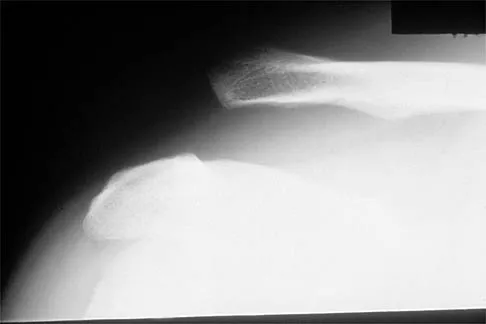

Question 12:

Figures 32a and 32b show the radiographs of a 13-year-old right hand-dominant boy who sustained a closed Salter-Harris type II fracture of the proximal humerus during a hockey game. The shoulder has significant swelling, but is neurovascularly intact. What treatment offers the best chance of reestablishing normal shoulder motion?

Correct Answer: Closed or open reduction and percutaneous pin stabilization

Explanation:

The patient has a significantly angulated proximal humerus fracture with a high degree of varus angulation, and rotational malalignment is likely. Failure to correct the varus angulation will result in permanent loss of shoulder abduction because the patient's age limits bony remodeling. These fractures are inherently unstable due to the inability to control the proximal fracture alignment. Shoulder spica casts have a high rate of redisplacement after treatment. Adequate open or closed reduction and pin fixation in the operating room optimizes alignment and all but eliminates the chance of redisplacement. Dobbs MB, Luhmann SJ, Gordon JE, et al: Severely displaced proximal humerus epiphyseal fractures. J Pediatr Orthop 2003;23:208-215. Vaccaro AR (ed): Orthopaedic Knowledge Update 8. Rosemont, IL, American Academy of Orthopaedic Surgeons, 2005, p 701.